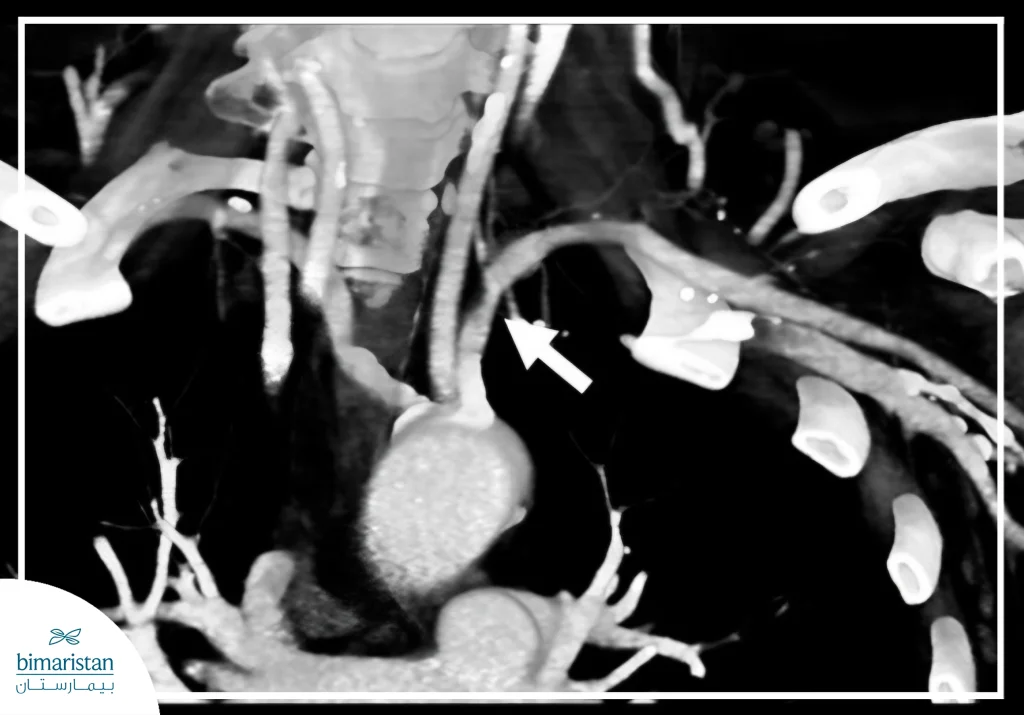

- التصوير الطبقي المحوري الوعائي (CT angiogram): يُستخدم للحصول على صور تفصيلية للشرايين باستخدام الأشعة المقطعية مع مادة ظليلة، مما يساعد على تحديد مكان التضيق وشدته بدقة.

- التصوير الوعائي التقليدي: فحص باضع يتم خلاله إدخال قسطرة رفيعة إلى أحد الشرايين وحقن مادة ظليلة لتصوير الشريان تحت الترقوة بشكل مباشر، وفي بعض الحالات تُستخدم تقنية الطرح الرقمي التي تساعد على إظهار الأوعية الدموية بوضوح أكبر عبر تقليل ظهور البنى غير الوعائية مثل العظام في الصورة.

تُظهر الصور (A–C) تسلسلاً لإجراء توسيع الشريان تحت الترقوة بالبالون مع وضع دعامة معدنية لإعادة فتح الوعاء وتحسين الجريان الدموي.